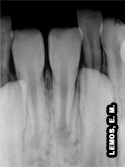

Características radiográficas do Incisivo Lateral Inferior esquerdo (32) |

Com relação aos comprimentos em milímetros dos incisivos laterais inferiores, podemos citar, máximo (29mm), médio (22mm) e mínimo (17mm), respectivamente |

| Direção da raiz | ||||

Reta: 54% Curvatura distal: 33% Curvatura vestibular: 11% Baioneta: 1% Angulação: 1% |

Características do canal no corte transversal:

Terço cervical, médio e apical: forma elipsóide com achatamento proximal

Número e forma radicular: raiz única, forma elipsóide com achatamento proximal, podendo determinar a presença de dois canais: vestibular e lingual